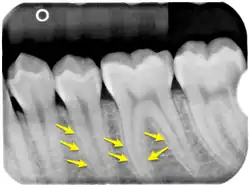

The lamina dura is a dense bone structure visible on dental radiographs as a thin, radiopaque border adjacent to the periodontal ligament and alveolar crest, forming part of the tooth socket.[10][11] Its role as "bundle bone" stems from its dense composition containing Sharpey's fibers, which develops during tooth formation as an egg-shell-like envelope and persists after eruption as a radiopaque layer.[10][8] Rather than being a radiographic artifact, studies confirm its appearance is determined by both structural properties and X-ray beam direction.[12][8] Several factors influence its radiographic visibility, including tooth position, root number, condition of the periodontal ligament, X-ray beam angulation,[13] anatomical structure superimposition, and film exposure times.[14] These variables can cause irregular appearances or apparent discontinuity, particularly in maxillary molars and premolars. Proper X-ray angulation, allowing rays to pass tangentially through the structure, enhances its visibility, while improper alignment or altered anatomy can obscure its appearance.[8][13]